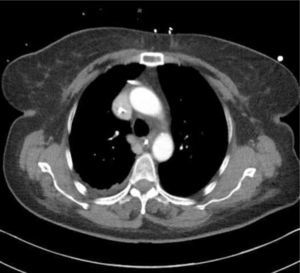

TOMOGRAFÍA COMPUTARIZADA AXIAL DEL TÓRAX

Se muestra cómo los vasos sanguíneos mamarios, pleura medial a la derecha, vena cava superior, aorta ascendente, y vena ácigos son todas similares en el primer y segundo plano. Los catéteres en cada una de estas diferentes estructuras no se distinguen claramente en el plano de la imagen (Radiografía de tórax).

Ante esta situación, los catéteres son fácilmente reconocidos como mal colocados y generalmente no se necesita el consejo de un especialista antes de su revisión, uso o retiro. Los catéteres pueden estar en una posición obviamente incorrecta fuera de la vena o puede parecer que siguen una ruta normal aproximada a través de la radiografía torácica, pero no están correctamente colocados en la vena cava superior. Las imágenes de tomografía computarizada axial muestran que no se pueden distinguir un catéter en una imagen plana el espacio pleural derecho, los vasos mamarios internos derechos, el sistema ácigo, la aorta ascendente o el mediastino (Figura 8). La radiografía torácica sólo puede confirmar el paso del catéter central, plegamientos de éste o complicaciones de procedimiento.